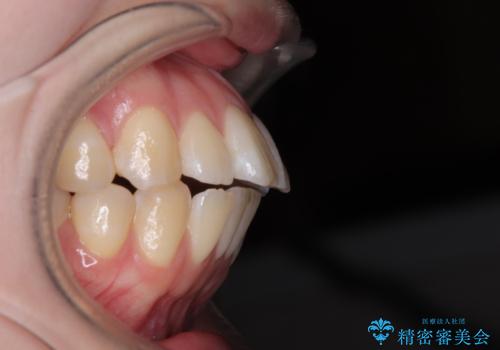

飛び出した前歯を引っ込める ワイヤー装置での抜歯矯正治療

- くちばしのように飛び出した前歯を気にして来院された患者様です。

上下左右の第一小臼歯4本を抜歯して、ワイヤー装置にて矯正治療を行うこととしました。

舌の突出癖により、口元が突出しているだけでなく、上下前歯が非接触となっておりました。

舌のトレーニングをしっかりと行っていただくことで、2年を切って治療を終えるとともに

、上下前歯を接触させることができました。